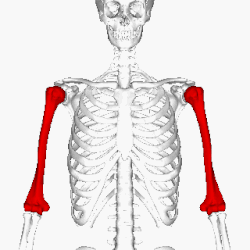

Перелом плечевой кости

Перелом плеча (переломы плечевой кости, лат. Fracturae humeri) — состояние, при котором происходит перелом (полный или частичный) тела плечевой кости (руки человека). Как правило, возникает при механических ударах или падениях, главным образом на локоть.

Кость довольно прочная, переломы плеча составляют всего 2,2 — 2,9 % среди всех переломов костей[2].